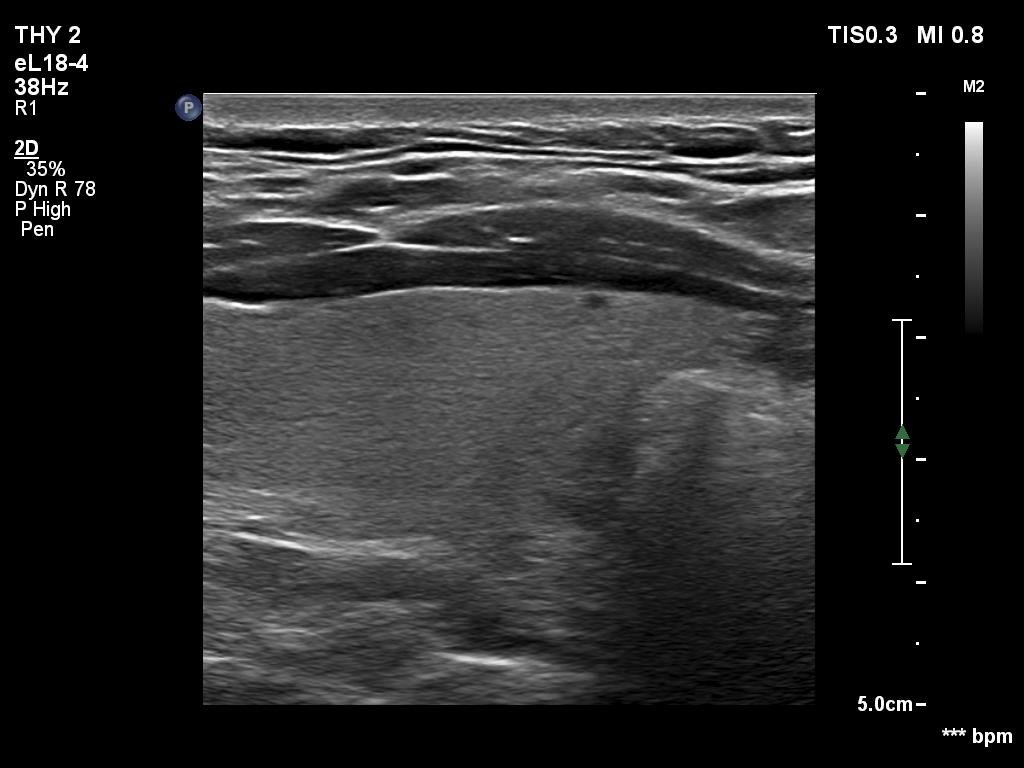

Ultrasonography. The thyroid was echonormal and had two cystic lesions in the left lobe. With higher frequency, the dorsal part of both lobes presented with hypoechoic blurred areas. With frequency decreased, these areas have disappeared.

Comment. This case illustrated the well-known inverse relation between penetrance and resolution. Better the former worst the latter and conversely. This has particular and practical importance if we examine obese patients using high-end equipment with high frequency. In such patients the obesity can significantly worsen the penetrance. This can be solved by decreasing the frequency and remove all software harmonization.